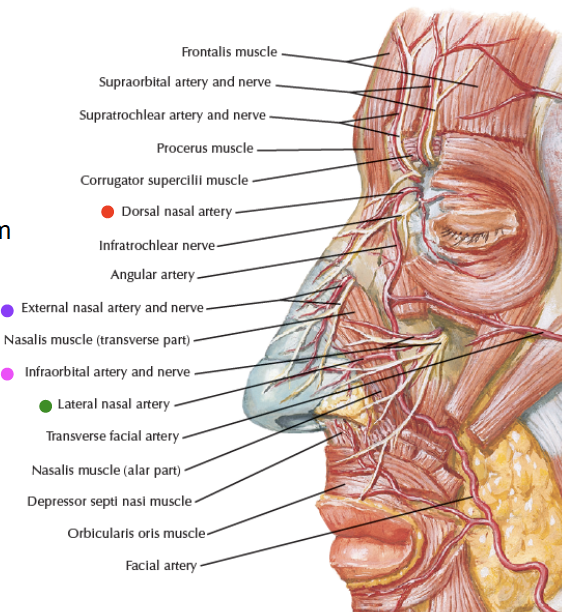

Artery

- Dorsal nasal a.

- External nasal a.

- Nasal br.

- Septal a.

- Alar a.

Nerve

- Ant. ethmoid n.

- Int./ Ext. nasal n.

- 鼻內/ 外感覺

- Int./ Ext. nasal n.

- Nasociliary br.

- Infraorbital n.

- Nasal br.

- Dorsal nasal a.